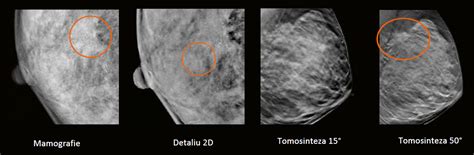

- Mamografia: Utilizează raze X și este considerată cea mai eficientă metodă de screening pentru depistarea precoce a cancerului de sân, în special pentru identificarea microcalcificărilor - un semn timpuriu al malignității. Este recomandată în mod special femeilor peste 40 de ani.

- Ecografia mamară: Folosește ultrasunete și este ideală pentru femeile tinere (sub 40 de ani), la care țesutul mamar este dens și poate masca leziuni la mamografie. De asemenea, este utilă pentru diferențierea între chisturi (formațiuni benigne pline cu lichid) și mase solide, pentru examinarea sânilor cu implanturi mamare și pentru investigarea inflamațiilor sau infecțiilor mamare acute.

În multe cazuri, ecografia mamară acționează ca o investigație adjuvantă, ajutând la clarificarea unor aspecte neclare identificate la mamografie sau la explorarea detaliată a unor leziuni suspecte.